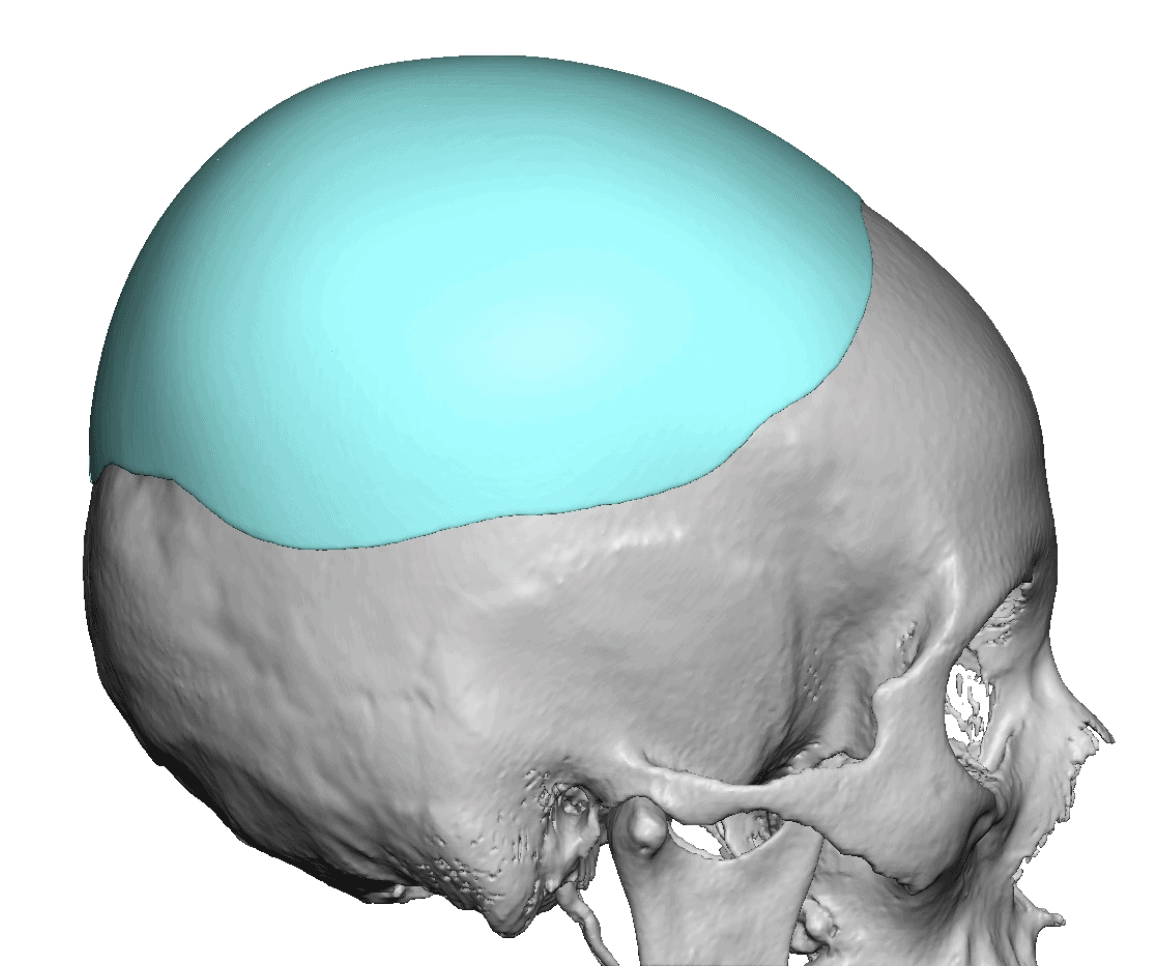

Patient 28

Desire for rounder shape to the top of the head from a congenital parasagittal deficiency skull shape.

Custom skull implant designed to fill in the parasagittal deficiencies.

Desire for rounder shape to the top of the head from a congenital parasagittal deficiency skull shape.

Custom skull implant designed to fill in the parasagittal deficiencies.